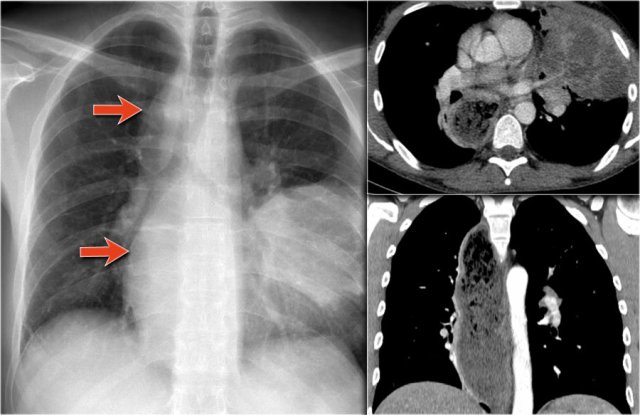

Another common cause of displacement of the azygoesophageal line is subcarinal lymphadenopathy.

Notice the displacement of the upper part of the azygoesophageal line on the chest x-ray in the area below the carina.

This is the result of massive lymphadenopathy in the subcarinal region (station 7).

There are also nodes on the right of the trachea displacing the right paratracheal line.

On the PET we can appreciate the massive lymphadenopathy far better than on the CXR.

There are also lymphomas in the neck.

this is an important finding, since these nodes are accessible for biopsy.

Here we see a CT-image.

The azygoesophageal recess is displaced by lymph nodes that compress the left atrium.

The final diagnosis of small cel lungcancer was made through a biopsy of a lymphnode in the neck.